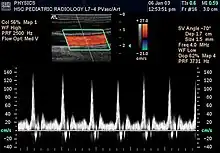

L'échographie Doppler est un examen médical échographique en deux dimensions non invasif qui permet d'explorer les flux sanguins intracardiaques et intravasculaires. Elle est basée sur un phénomène physique des ultrasons : l'effet Doppler. Elle est souvent surnommée écho Doppler.

- Le mode pulsé :

la mesure s'effectue sur le déphasage émission/réception. La sonde fonctionne alternativement comme émetteur et comme récepteur. Il est possible de régler la période de la pulsation ce qui permet de sélectionner la profondeur de la zone explorée. Le flux enregistré est donc mieux repéré sur l'image. En revanche, les flux très rapides, au-delà d'une vitesse maximale mesurable, ne peuvent pas être enregistrés en Doppler pulsé.